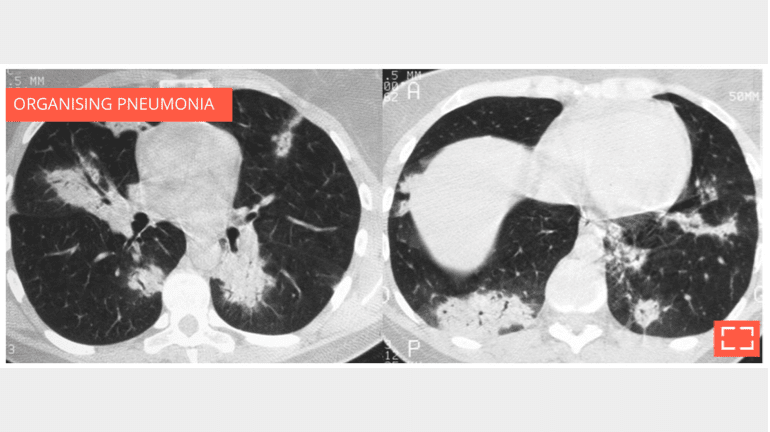

• organising pneumonia (possible migration)

Bilateral subpleural alveolar consolidation with air bronchogram, in a patient with chronic cough.

• Note whether the foci migrate between the two scans, strengthening the argument for organising pneumonia.